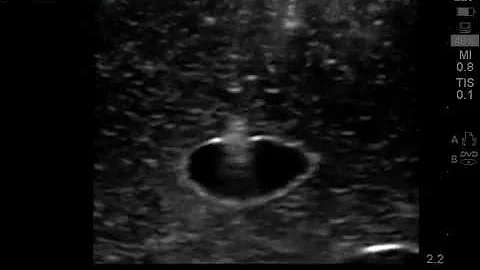

Pocus Guided Vascular Access Fundamentals: In-plane, Long Axis

This brief video details techniques for obtaining vascular access with POCUS guidance using an out-of-plane technique, targeting ...